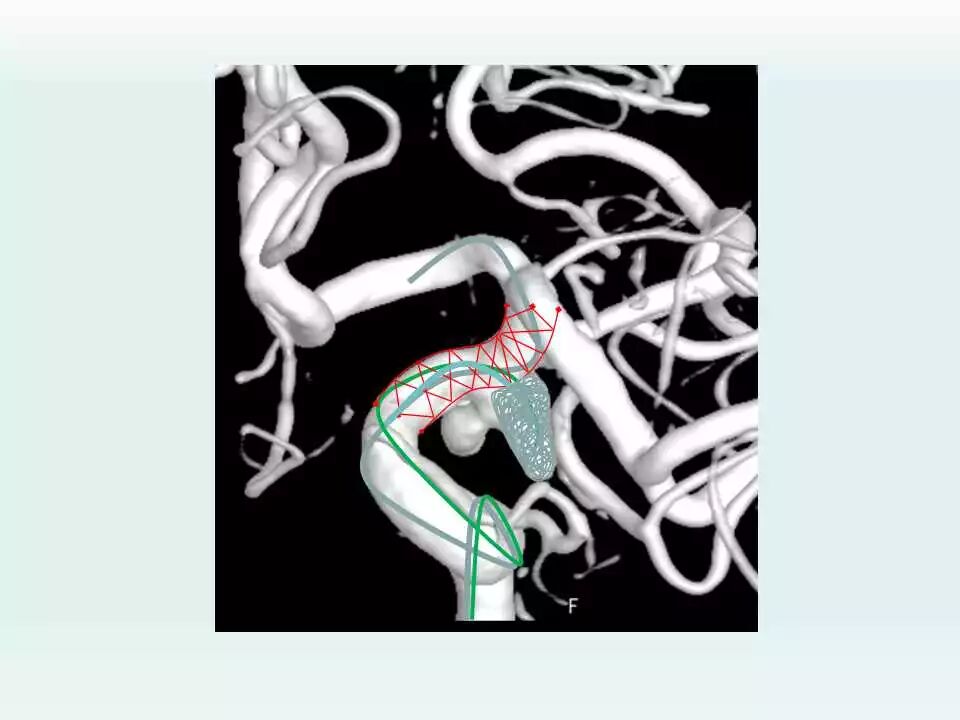

2003年开始神经介入工作,5年前在安徽省率先成立脑血管亚专业病区,每年的脑血管造影和血管内治疗颅内动脉瘤、脑动静脉畸形、颈内动脉海绵窦瘘及硬脑膜动静脉瘘等出血性疾病达1000台,并形成了急性期支架辅助弹簧圈治疗破裂宽颈动脉瘤、微小动脉瘤的血管内治疗和复杂动脉瘤的血管内治疗的特色,目前年血管内治疗颅内动脉瘤300例以上。